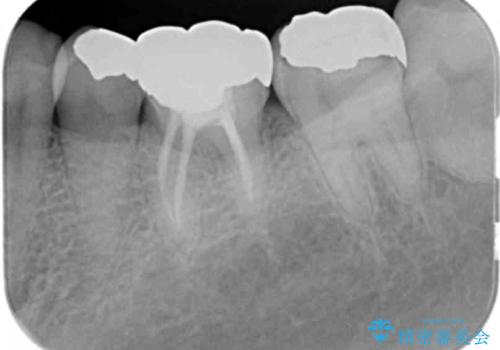

目立つ銀歯を白くしたい

- 「笑った時に目立つ銀歯をきれいにしたい、皮膚科で金属アレルギーの可能性を指摘されたので金属を外したい。」

、とセラミック治療を希望され来院されました。

残っている歯を削らないよう、丁寧に除去したのち精密なジルコニアセラミッククラウンで再咬合構成を行っていきます。